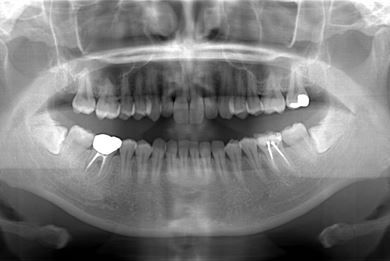

インプラントの症例写真 IMPLANT

インプラント治療

| 主訴 | 銀歯がはずれた奥歯にひびが入っており、抜歯しなければいけないため、インプラントの治療相談を希望。 | ||||||||||||||||||||||||||||||||

| 治療内容 | インプラント1本、メタルボンドセラミック1本 | ||||||||||||||||||||||||||||||||

| 総治療費 | 401,363円 | ||||||||||||||||||||||||||||||||

| 治療期間 | 5ヶ月 |